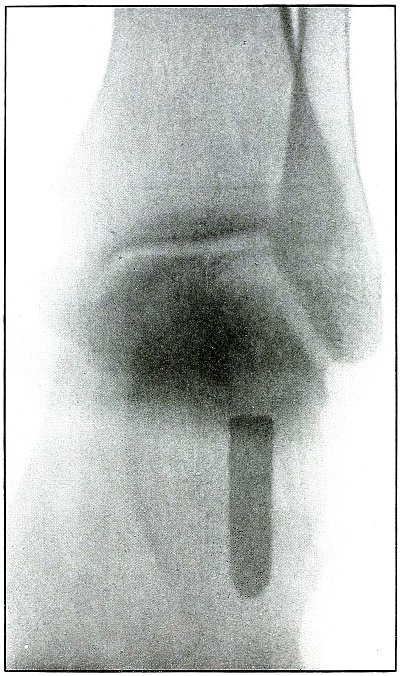

Rifle—Plate 10.

UPPER EXTREMITY.

Gunshot Fracture of the Left Humerus,

with Lodgment of the Missile.

Wound of entrance, anterior surface of upper third of the arm.

Wound of exit, none.

The shadow of the missile shows by its distinct outline and normal

diameter at the tip that the missile lies on the side near the plate;

the shortened length of the projectile indicates that the long axis

lay in an acute angle with a perpendicular to the plate.

The irregular outline of the base of the shadow and the fact of

lodgment shows that the missile was deformed and that it was

incidentally retarded in velocity by ricochet, so that its penetrating

force was not sufficient to carry it through the arm.

The fragments of bone are large and the wound is of the same character

as might have resulted from a shrapnel ball, for the normal ballistic

conditions of the latter simulate the conditions that produced the wound.

The drainage tubes seen in the plate indicate infection.

The conventional treatment in such cases is drainage and other

management of the infection without formal search for the projectile.

Results should be favorable.